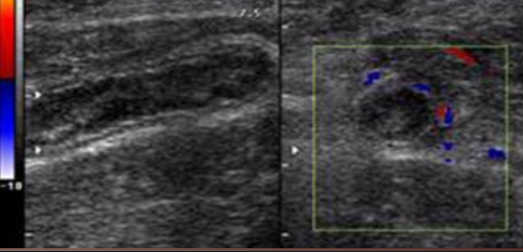

Duplication cyst

Leiomyoma